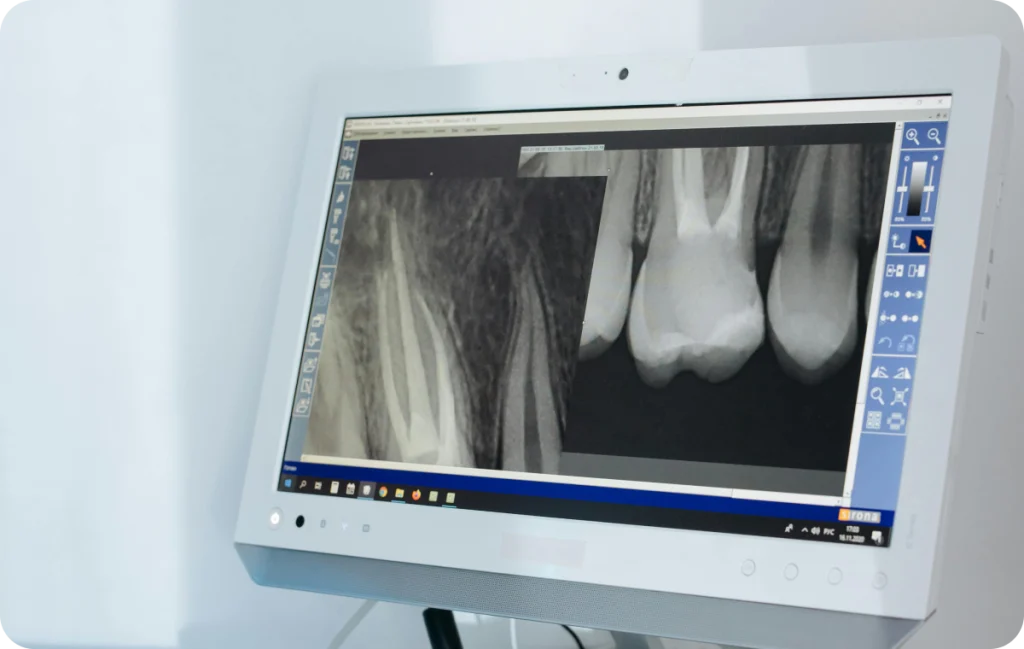

Le rôle de l’imagerie dans le traitement de racine

L’imagerie accompagne chaque étape du traitement de racine. En effet, les radiographies permettent d’anticiper les difficultés liées à l’anatomie de la dent. De plus, elles aident à vérifier la qualité du nettoyage et de l’obturation des canaux.

Après le soin, des contrôles radiographiques peuvent également être réalisés. Ainsi, le praticien s’assure de la bonne évolution des tissus autour de la dent. Grâce à ce suivi, il devient possible de confirmer la stabilité du traitement dans le temps.

Parfois, le praticien détecte une infection uniquement grâce à un examen radiographique. En effet, une image peut révéler une atteinte autour de la racine de la dent. Par ailleurs, un gonflement de la gencive, un petit bouton ou un changement de couleur de la dent peuvent apparaître. Ces signes doivent inciter à consulter afin d’évaluer la situation.

Avant de débuter le traitement de racine, le praticien réalise un examen clinique et radiographique. Grâce à ces éléments, il identifie le nombre de racines et la forme des canaux. Ensuite, il procède à une anesthésie locale afin d’assurer le confort du patient pendant toute la durée du soin.